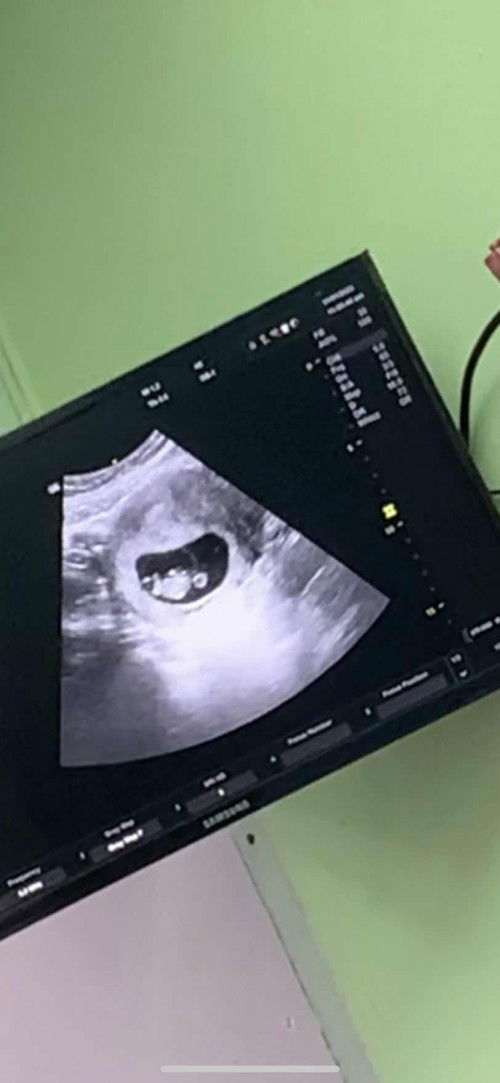

hai semua saya nak tanya , masa saya scan doc kata ada kantung dalam kantung , tapii satu lagi kantung macam ada bulat , tapi taknampak baby dalam tu , so doc kata mungkin macam kantung tak menjadi , incase kalau takjadi , dia akan turun darah ke ? atau dia hilang sendiri ? kalau hilang sendiri tu macamnaa , dia jatuh turun darah ke , atau hilang macamtu je ? saya takut jugak , sebab sekarang saya dah 11 minggu , takada apa apa turun darah . #pleasehelp #bantusharing